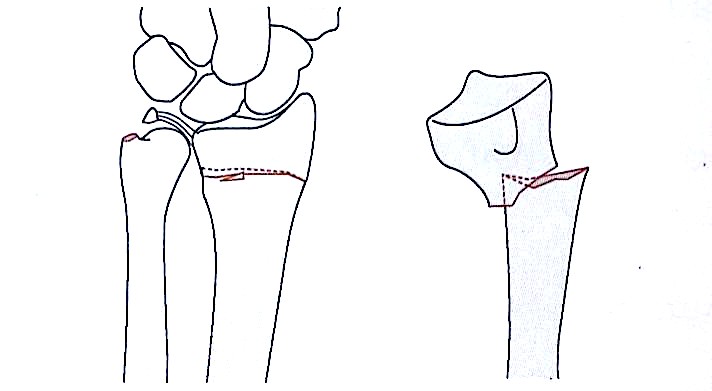

Metafizni fleksijski zlom tipa I

Sklepni in strižni zlom tipa II

Kompresijski zlom sklepne površine tipa III

Tip IV avulzijski zlom radialnega zapestja, izpah

Mešani zlomi tipa V (visokoenergijski avulzijski zlomi)